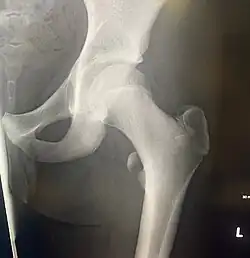

The lesser trochanter can be involved in an avulsion fracture.[4]